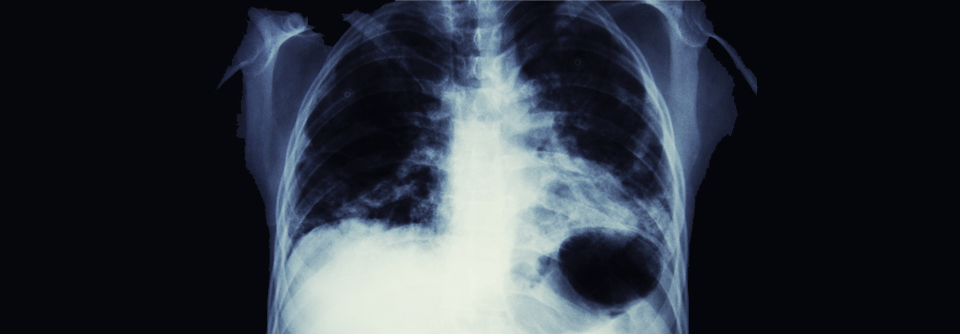

Lungenkarzinom

Lungenkrebs hat trotz aller Fortschritte in Diagnostik und Therapie nach wie vor eine schlechte Prognose. Angesichts dessen leiden viele Betroffene…